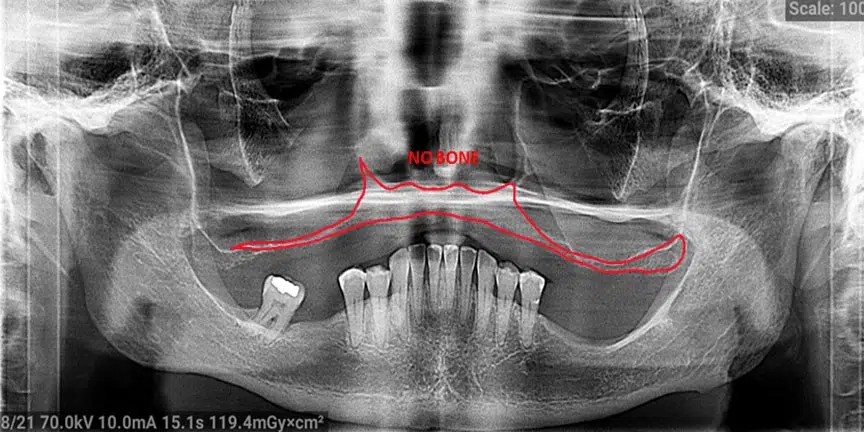

Challenging Cases

- We provide treatment for patients when other providers are unable to handle their cases.

Severe Bone Loss